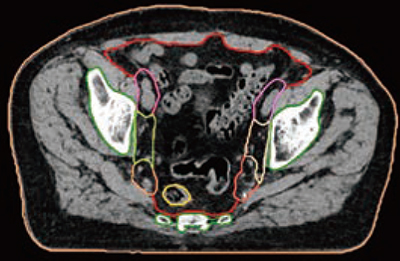

■放射線治療計画支援

AIを駆使した技術は,放射線治療計画支援においても有効活用されている。syngo.viaの「RT image Suite(RTiS)」は,放射線治療計画支援システムとしてデフォーマブルレジストレーションや4Dにおけるコンツーリングなど,さまざまな放射線治療計画支援機能を有しているが,その中でも評価が高いのが,Auto Contouringの機能を司る「Organs RT」である。現在対象となる臓器は85を超えており,頭頸部や肺野などにおける単なる抽出精度正確性だけでなく,骨盤内リンパ節(図2)などガイドラインに沿った形での臓器抽出ができることについても高い評価を得ている。このAuto ContouringもRRTと組み合わせることが可能で,CTデータを受信すると同時に事前に紐付けたテンプレート設定に従ってAuto Contouringを実施し,作成されたRT Structureのデータを放射線治療計画システムに自動送信することができる。その精度の高さから,RTiSやOrgans RTを活用することでコンツーリングの時間が大幅に低減できることも報告されている。

図2 骨盤部のAuto Contouring結果